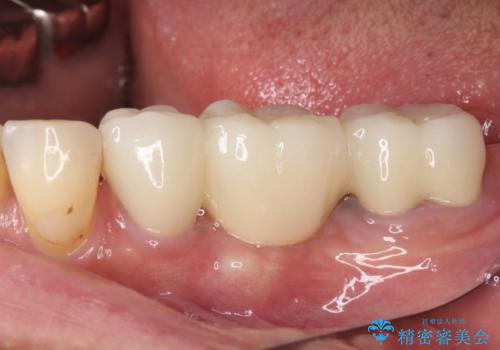

抜歯をしたことで、ずっと気になっていた異臭から解放されました。

前後の歯はいずれも神経が取り除かれている歯であったので、ブリッジ治療では負担が大きくなることが懸念されました。咬合力はさほど強くない咬み合わせであったので、インプラントではなく、ブリッジ治療を選択されました。